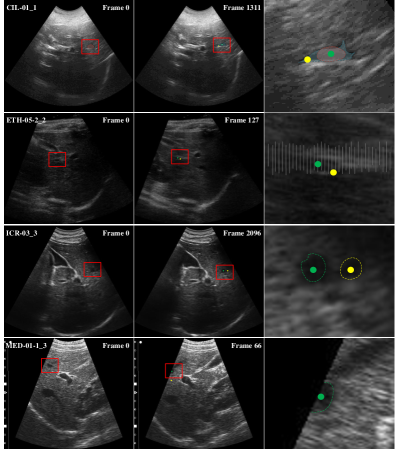

Refer to caption

Figure 2: Illustration of Long-Short Diffeomorphic Motion. Top row denotes an example of the input image set. From top-left to top-right: Frame 0 serves as the fixed template for long range deformation. Frame tβˆ’Ξ”β€‹t𝑑Δ𝑑t-\Delta t serves the moving target for long range deformation, also adaptive template for short range deformation. Frame t𝑑t serves the short range target. From bottom-left to bottom right: Long range diffeomorphism vector; Short range diffeomorphism vector; Illustration of joint long-short diffeomorphism motion (blue: short range deformation, yellow: long range deformation; red: cumulative error from single range deformation).